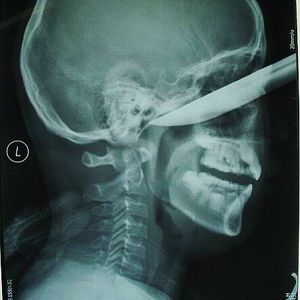

This 13-year-old Chinese teenager slipped down and stabbed himself in the face with a 20cm-long knife while peeling an apple. He was referred by the local hospital to a larger surgical unit. The knife, which is more than 20cm long, penetrated 7cm into his face. Fortunately, the surgery was successful and the patient could recover fully in around a month.